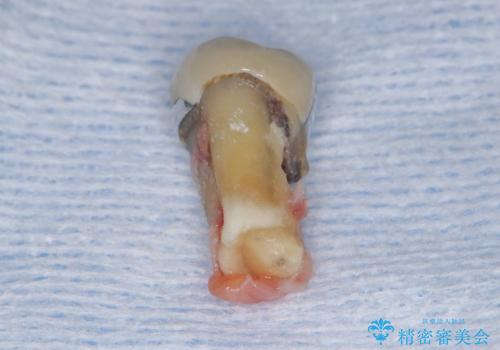

- 過去にヘミセクションが行われていたと思われる左下7番は、大きな歯根嚢胞および根尖病変が認められ、さらに骨縁下カリエスを伴っており、歯肉には瘻孔が形成されている状態でした。

保存は困難と判断し、左下7番は抜歯即時インプラントによる治療を行いました。